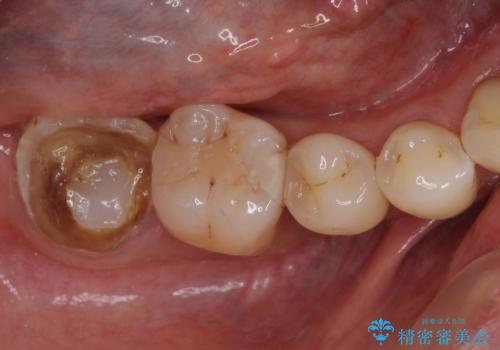

- 奥歯の詰め物が取れ、近医で再装着してもらったものの、すぐに脱落してしまったとのことで来院された患者様です。

既に神経は失活していましたが根管治療はされておらず、むし歯が大きかったためか、歯全体が手前に動いてしまっていました。